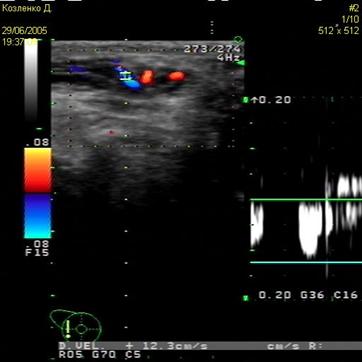

реверс в венозном кровотоке